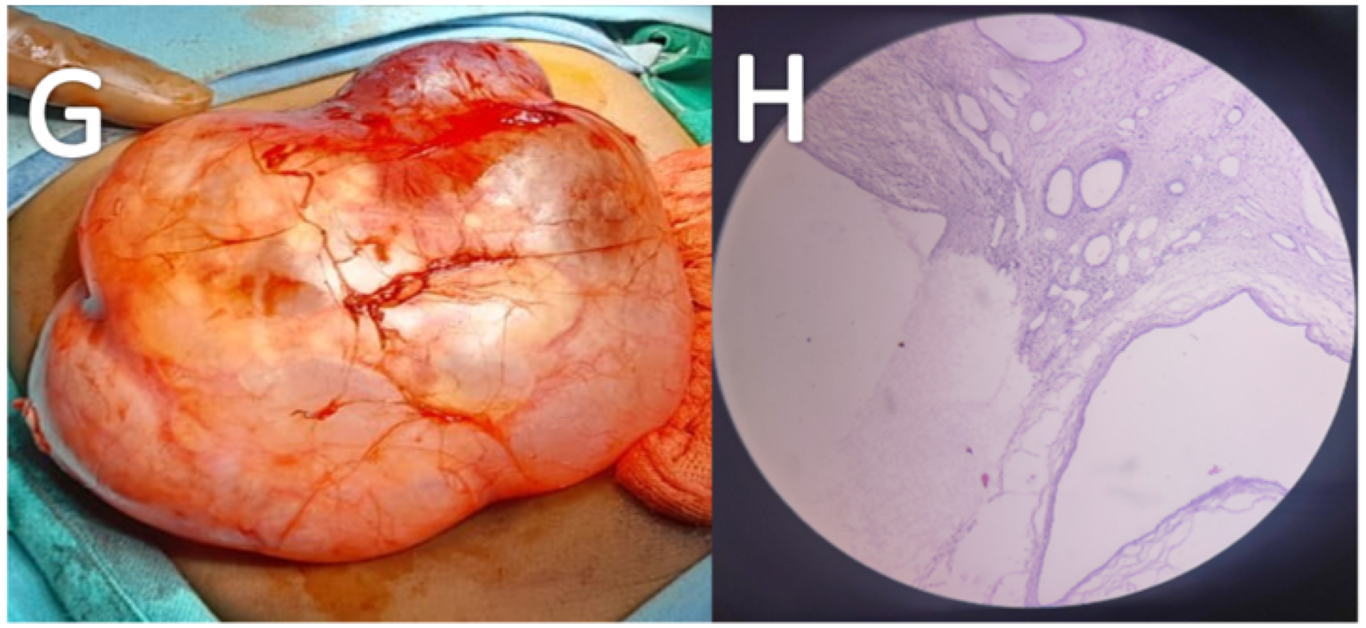

The patient was advised for USG abdomen. USG revealed a large cystic lesion with multiple thin echogenic internal septations in the right flank arising from the right kidney (Figure A). The residual right kidney was displaced medially and anteriorly. She underwent a contrast-enhanced CT scan on a 128 slice Siemens machine. On CT, there was a well defined multiloculated cystic lesion of size approx. (12.5 x10.9 x10.5) cm is seen in the right renal fossa. Multiple thick enhancing septations were observed in the lesion. A Claw sign was depicted with the adjacent right kidney suggesting an organ of origin. Residual right renal parenchyma was pushed anteromedially, showing mild hydronephrosis due to pressure effect. Renal vasculature and adjacent great vessels were unremarkable (Figure B, C, D, E). MRI was advised for better evaluation of fat planes with surrounding structures. Multiparametric and multi sequential MRI was performed over a 1.5 Tesla Siemens machine (Somatom 2014 model) using the surface coil. It revealed multiple cysts with thick septations within the lesion. The contents of the cysts appear hypointense on T1 hyperintense onT2WI. No obvious capsular breach/invasion into surrounding tissue was noted (Figure F).

Figure A- USG image illustrates a cystic lesion with multiple internal thick septations.

Figure B- Non-contrast CT axial scan shows a well-defined fluid density lesion showing internal septations in the right renal fossa region.

Figure C, D & E- Contrast-enhanced CT scan axial view (C &D) and coronal image (E) shows a well-defined multiloculated cystic lesion with thick internal septations in the right renal fossa region. Residual right renal tissue is seen displaced anteromedially. “Claw sign / Beak sign” is depicted with adjacent right kidney suggesting organ of origin.

Figure F- Non-contrast MRI abdomen T2WI shows a well-defined multiloculated cystic lesion.